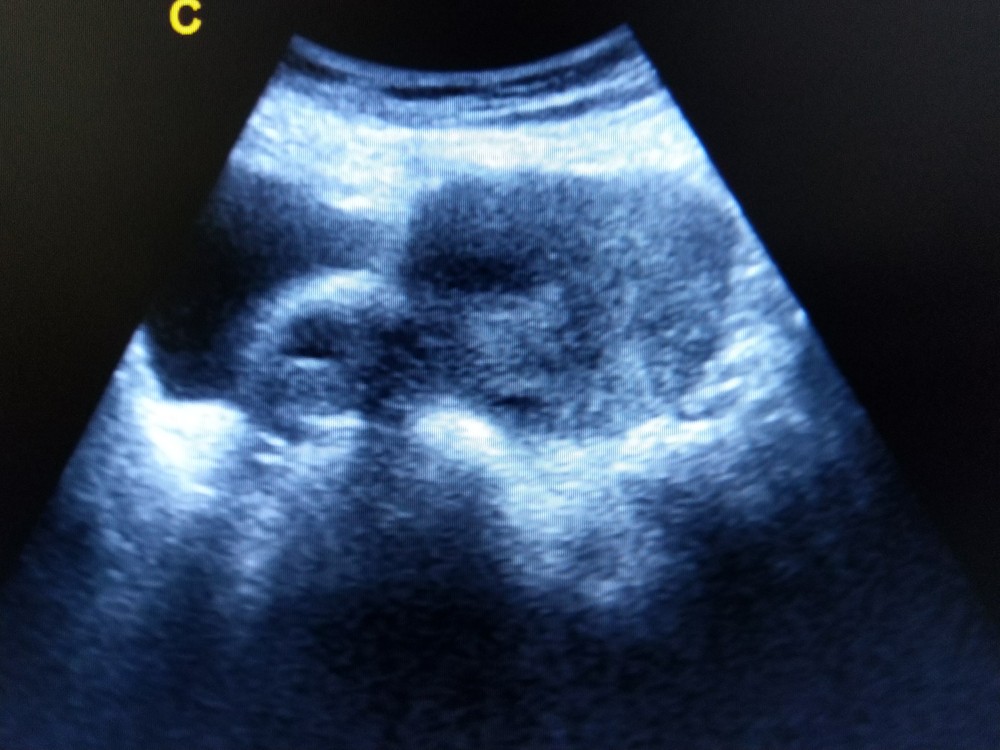

【卵巢囊腫】水瘤、肉瘤、血瘤有何分別?有分良性和惡性?一定要手術治療嗎?

卵巢囊腫簡單分為三種:水瘤、肉瘤、血瘤。有些是良性腫瘤,無需動手術就能夠自然痊癒,但有些一旦惡性腫瘤若不及時治療,可能會導致不孕,嚴重甚至可能會出血或致癌。